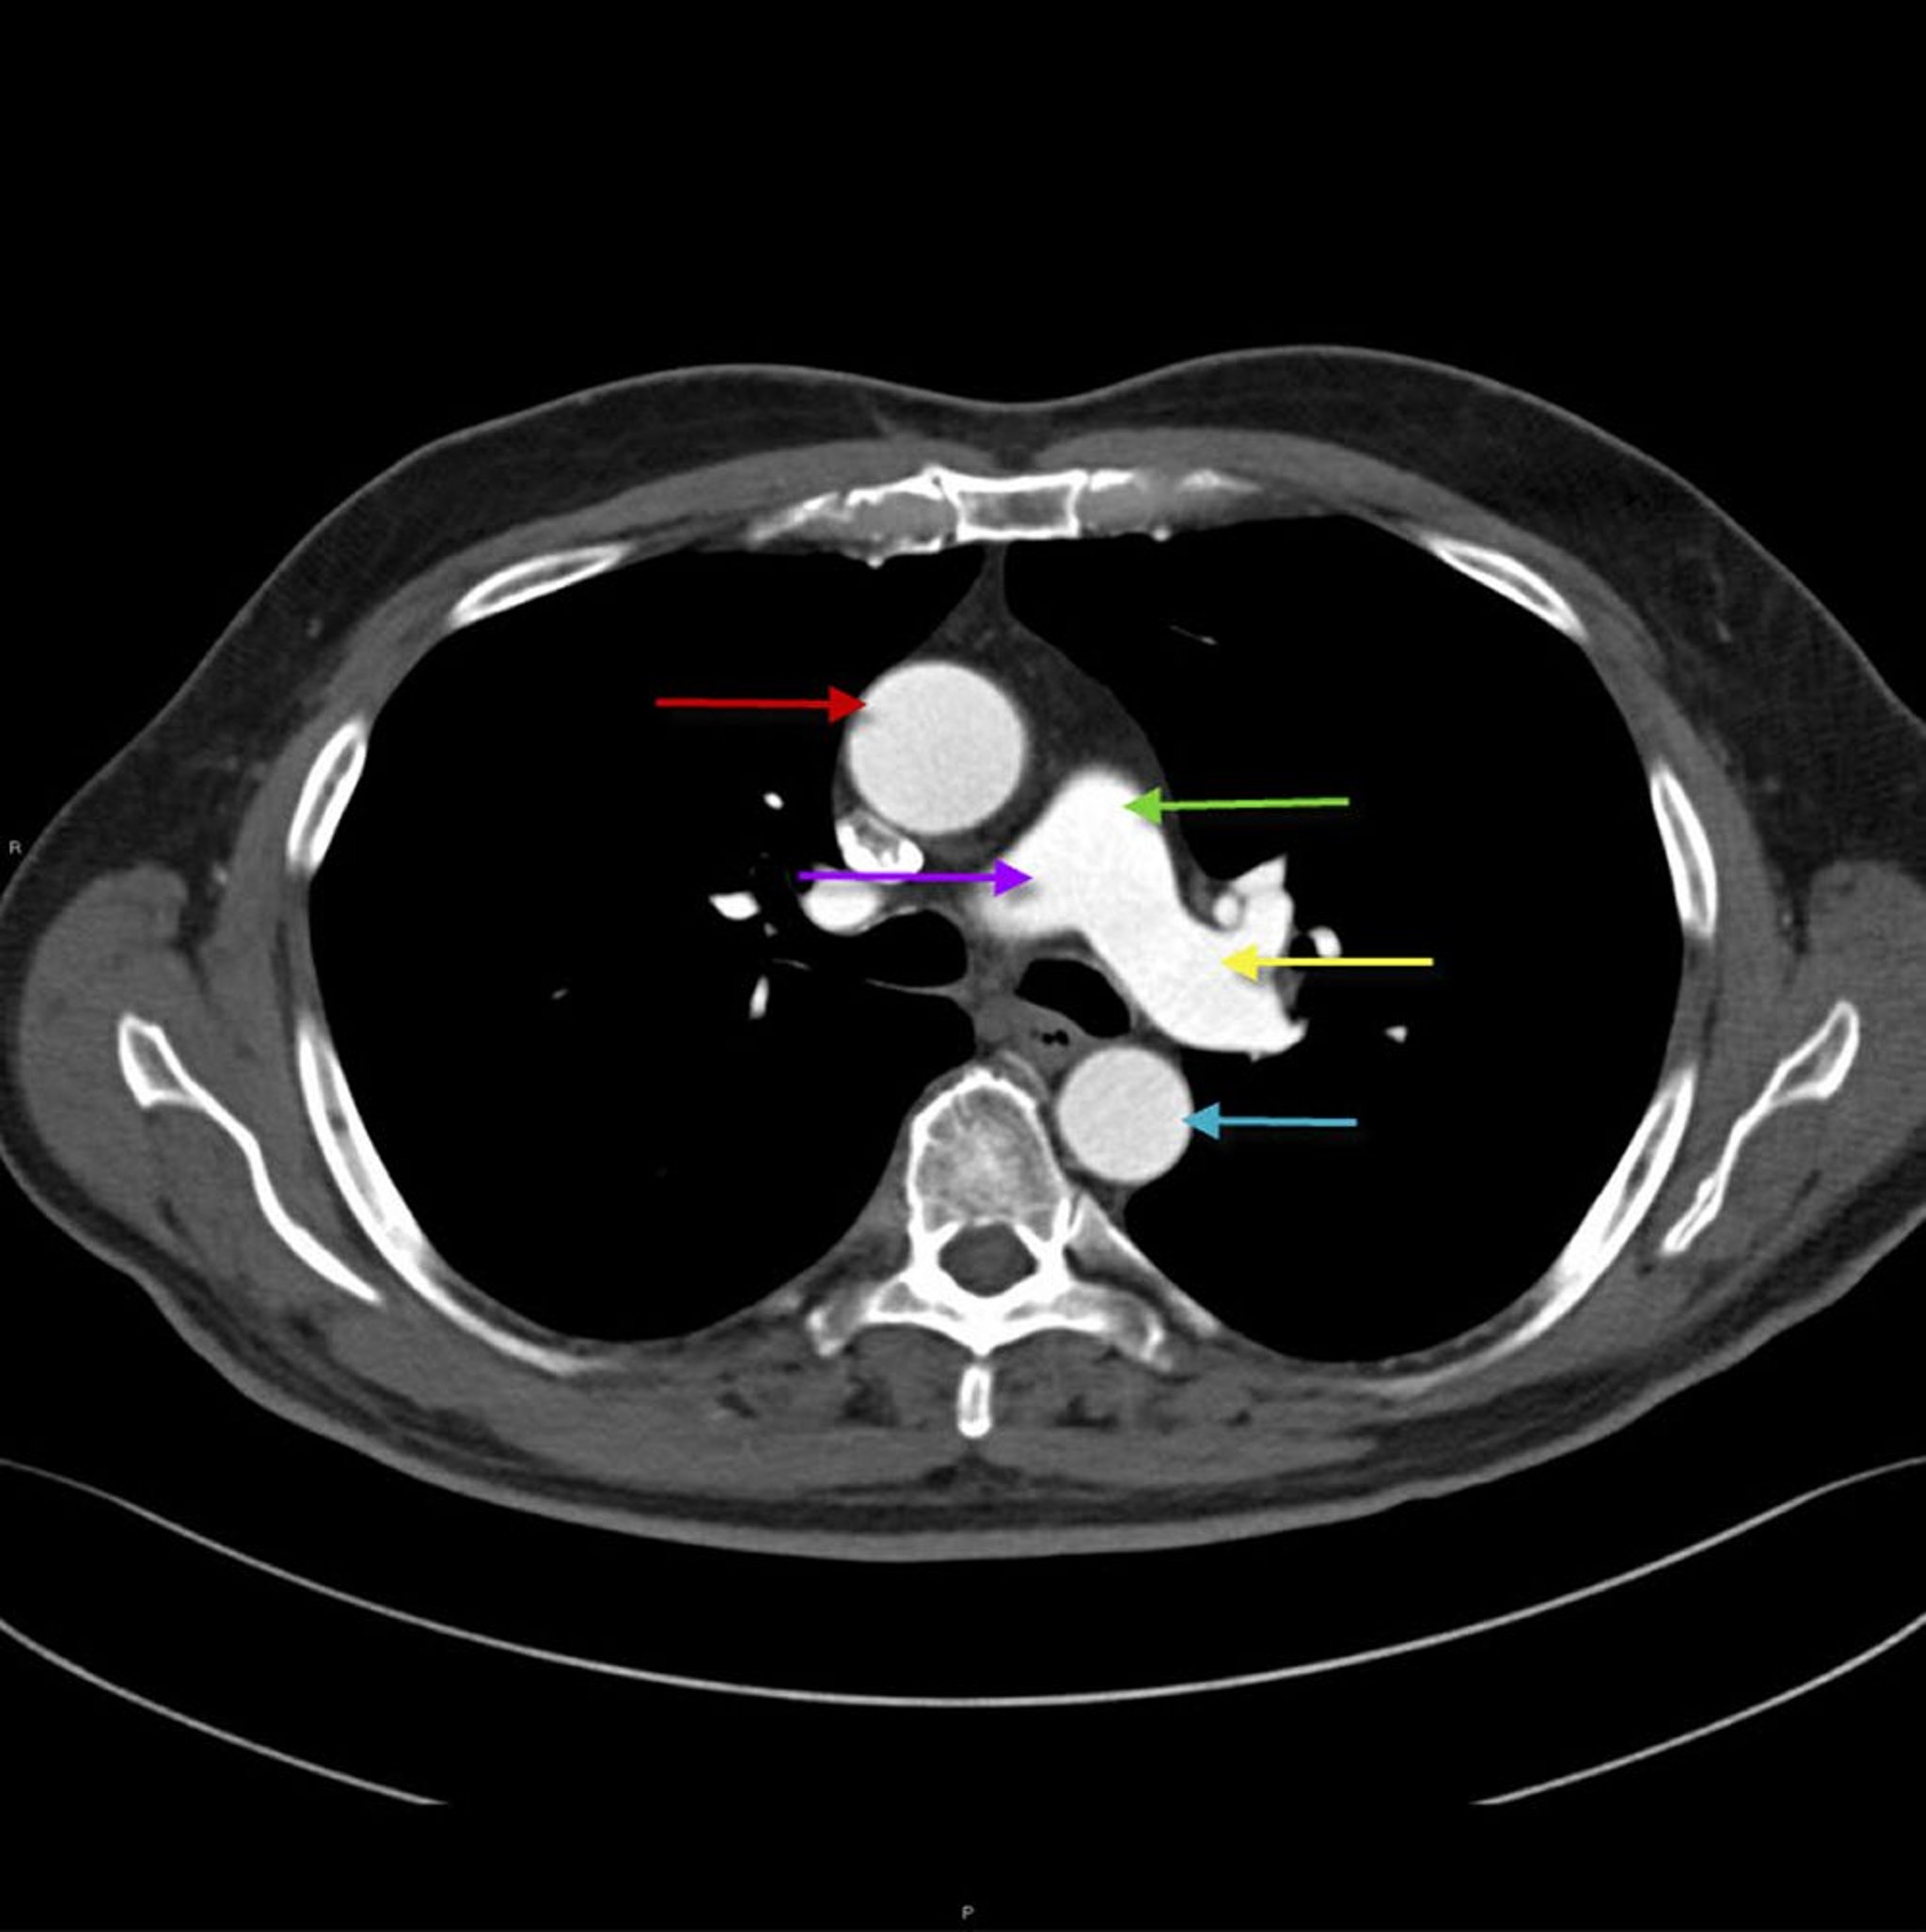

КТ грудной клетки, показывающая анатомическое строение аорты и легочной артерии

Данное изображение показывает восходящий отдел грудной аорты (красная стрелка) и ее нисходящий отдел (синяя стрелка). Легочной ствол (зеленая стрелка) делится на правую (фиолетовая стрелка) и левую (желтая стрелка) легочную артерию.